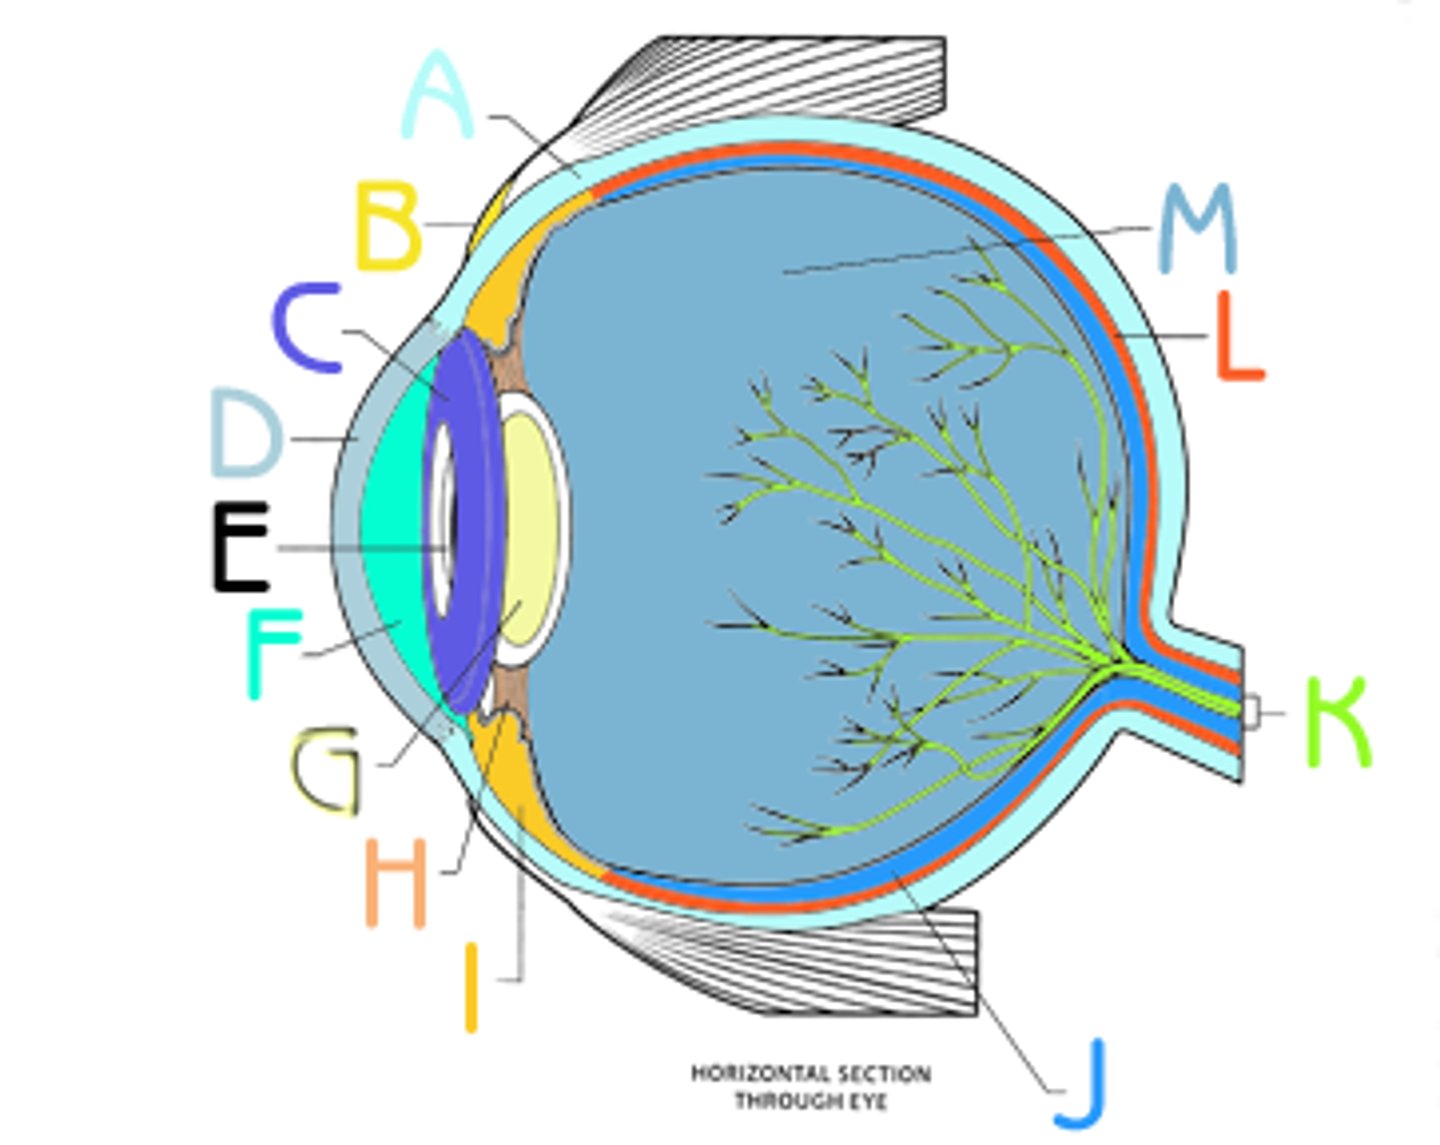

anterior cavity (of eye)

iris

B

optic disk (blind spot)

choroid

L

ciliary body

B

ciliary process

conjunctiva

cornea

D

fovea centralis

suspensory ligaments

C

vitreous humor

lens

H

macula lutea

posterior cavity (of eye)

pupil

F

retina

M

sclera

optic nerve